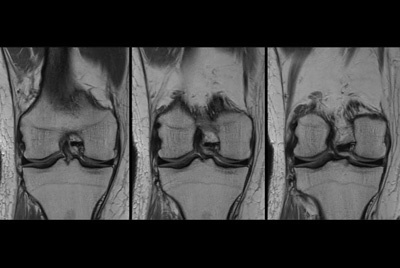

SmartSpeed Traumatic Knee imaging

SmartSpeed 2 min Knee imaging

Knee ACL repair

Knee with lesion

High quality Knee imaging in short scan times

Knee imaging with Compressed SENSE

Knee exam with/without Compressed SENSE

Knee Imaging with Cartilage Assessment

Metal Imaging of the Knee

3D Knee imaging with MSK VIEW

Knee imaging

Comprehensive 3D knee imaging with MSK VIEW